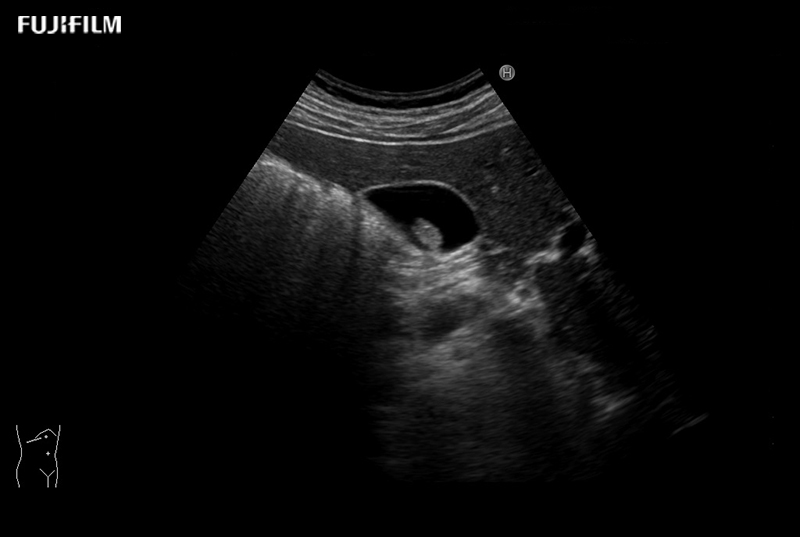

Contrast-specific software is supported for use with contrast agents used with acoustic pressures from low to mid Ml. This is compatible with various transducers.